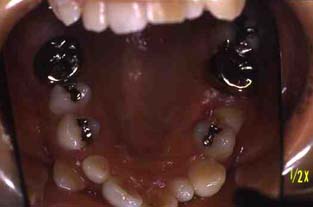

成人その3:八重歯と顎が狭い(唇側低位咬合,歯列狭窄) 22才,女性

上顎

(ミラー像)

下顎